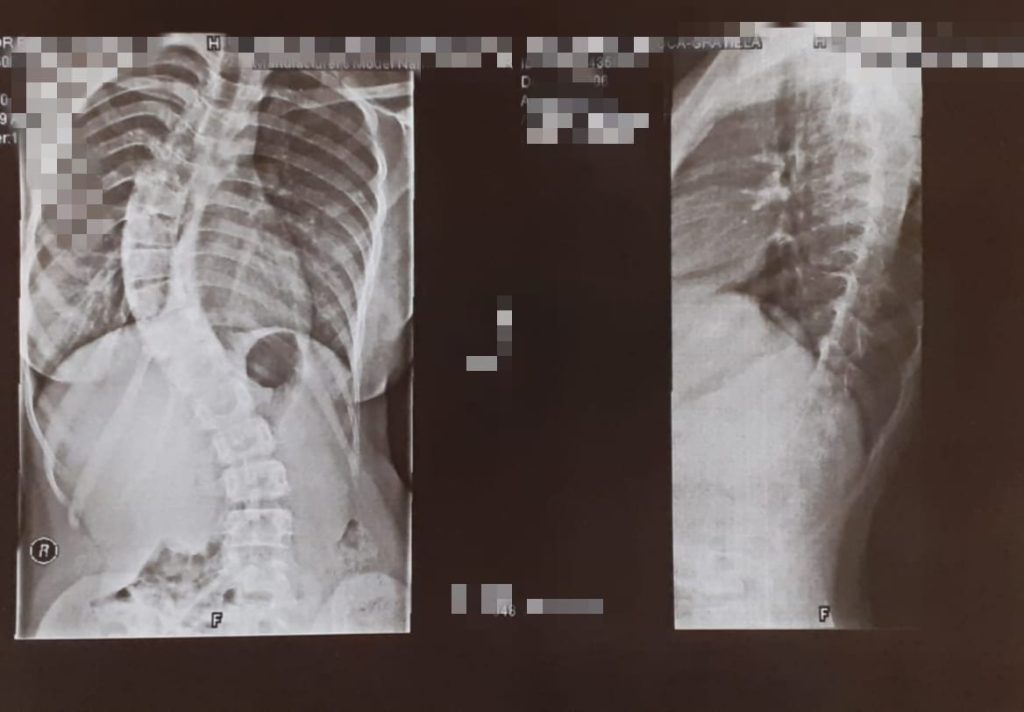

In imagine avem o frumusețe de fata de 17 ani care a ajuns in mod accelerat cu acest grad de scolioza ,chiar daca s-a acționat imediat cu tot ce se poate în acest sens . Uneori suntem prea ,,mici” pentru a înțelege propriul corp ,dar mereu am susținut că ???????????????????????????? să ținem cont de primele semne de ????????????????????????̆ și că ???????????????????? ???????????? ???????? ???????????????????????????????????? ????????????????????????̦???????? ???????? ???????? ???????????????????????? ???????????????????????????????????????????????????????????? ????????????????????????̆ .